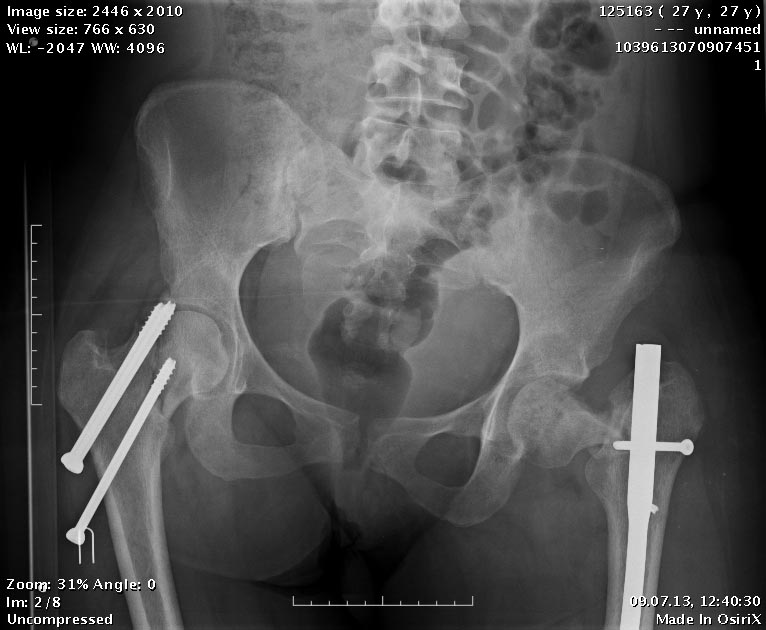

Пациентка приехала на этой неделе. Сегодня сделали правое бедро. Удалили

винты, сделали чрескожную вальгизирующую остеотомию, зафиксировали

Affixus. Второе бедро будем делать недели через 2.